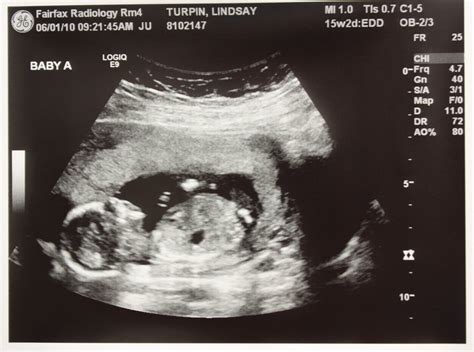

Understanding the Ultrasound Images

The 16 week ultrasound provides detailed images of the baby’s anatomy. Healthcare providers will look for specific features to ensure everything is developing normally. Some of the key areas of focus include:

• Limbs: The length and structure of the arms and legs, including the hands and feet.